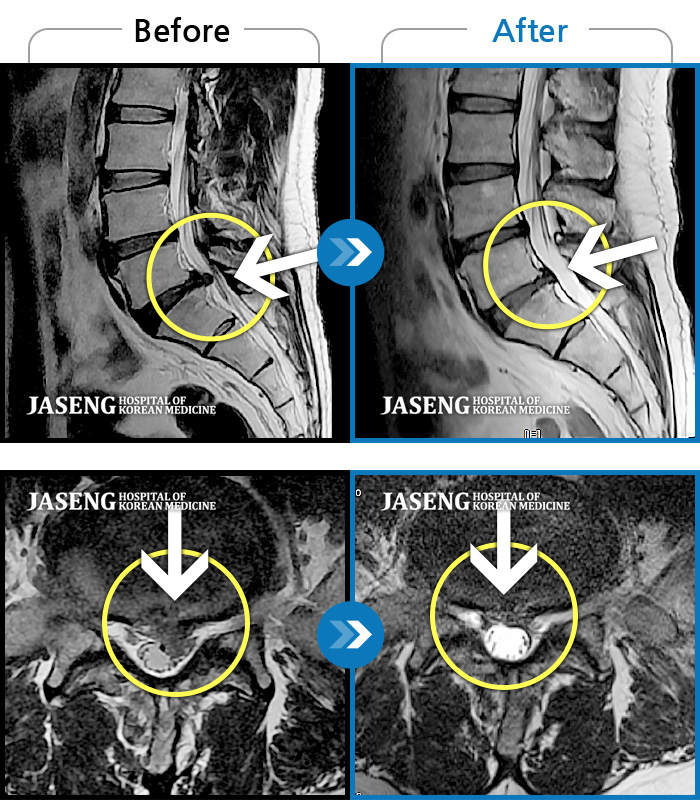

MRI 치료사례

모든 자세에서 지속적으로 좌측 엉치, 허벅지, 종아리 후면, 외측, 발가락 끝까지 저리고 아프다.